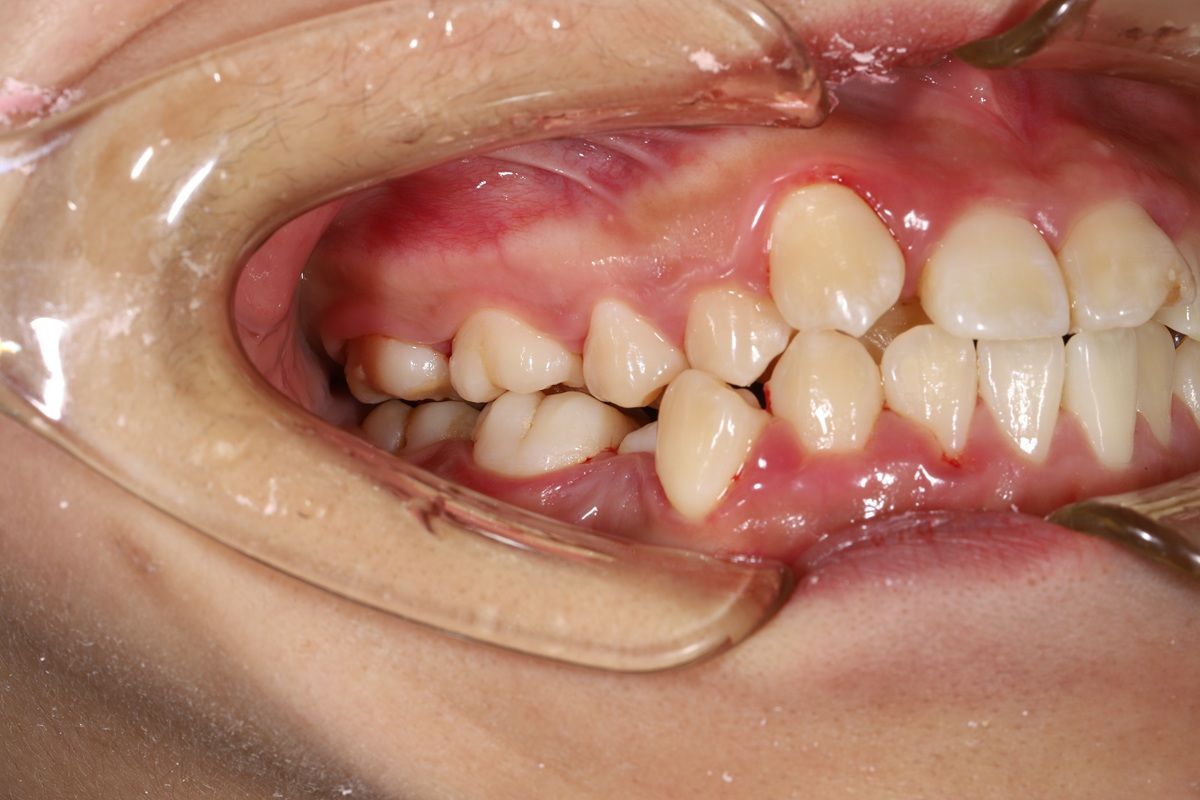

Qua thăm khám lâm sàng và chẩn đoán hình ảnh tại Nha khoa Hanseoul, bác sĩ ghi nhận các vấn đề chính:- Răng chen chúc, khấp khểnh, răng mọc lệch khỏi cung hàm.

- Thiếu khoảng sắp xếp răng, khiến răng xoay và chồng chéo.

- Khớp cắn đối, ảnh hưởng đến chức năng ăn nhai và độ cân đối gương mặt.

- Nụ cười chưa hài hòa, đường cười và tương quan hai hàm chưa chuẩn.